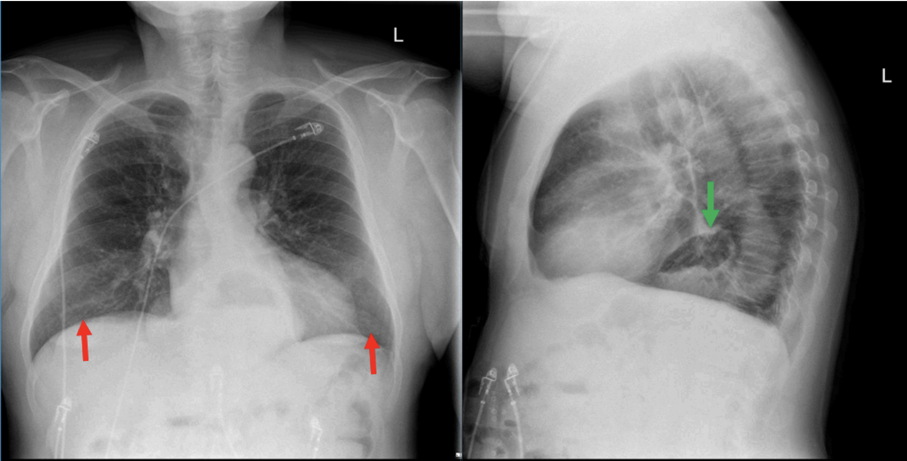

Μία άλλη μέθοδος με την οποία μπορεί να αναδειχθεί η παρουσίαδιαφραγματοκήλης είναι η ακτινολογική απεικόνιση. Η απλή ακτινογραφία θώρακα σε σπάνιες περιπτώσεις μπορεί να είναι χρήσιμη, καθώς απεικονίζεται η γαστρική φυσαλίδα δηλαδή ο αέρας του εσωτερικού του στομάχου μέσα στο θώρακα. Η μέθοδος που χρησιμοποιείται συνήθως είναι η ακτινολογική απεικόνιση μετά την κατάποση βαρίου, ενός σκιαγραφικού υλικού. Με αυτόν τον τρόπο απεικονίζεται ακτινολογικά ο πεπτικός σωλήνας και αποκαλύπτεται ηδιαφραγματοκήλη. Σε κάθε ακτινολογικό έλεγχο με βαριούχο γεύμα ο ασθενής τοποθετείται σε θέση TRENDELEBURG 20 μοιρών (κεφάλι κάτω) έτσι ώστε να αναδειχτεί η γαστροοισοφαγική παλινδρόμηση.